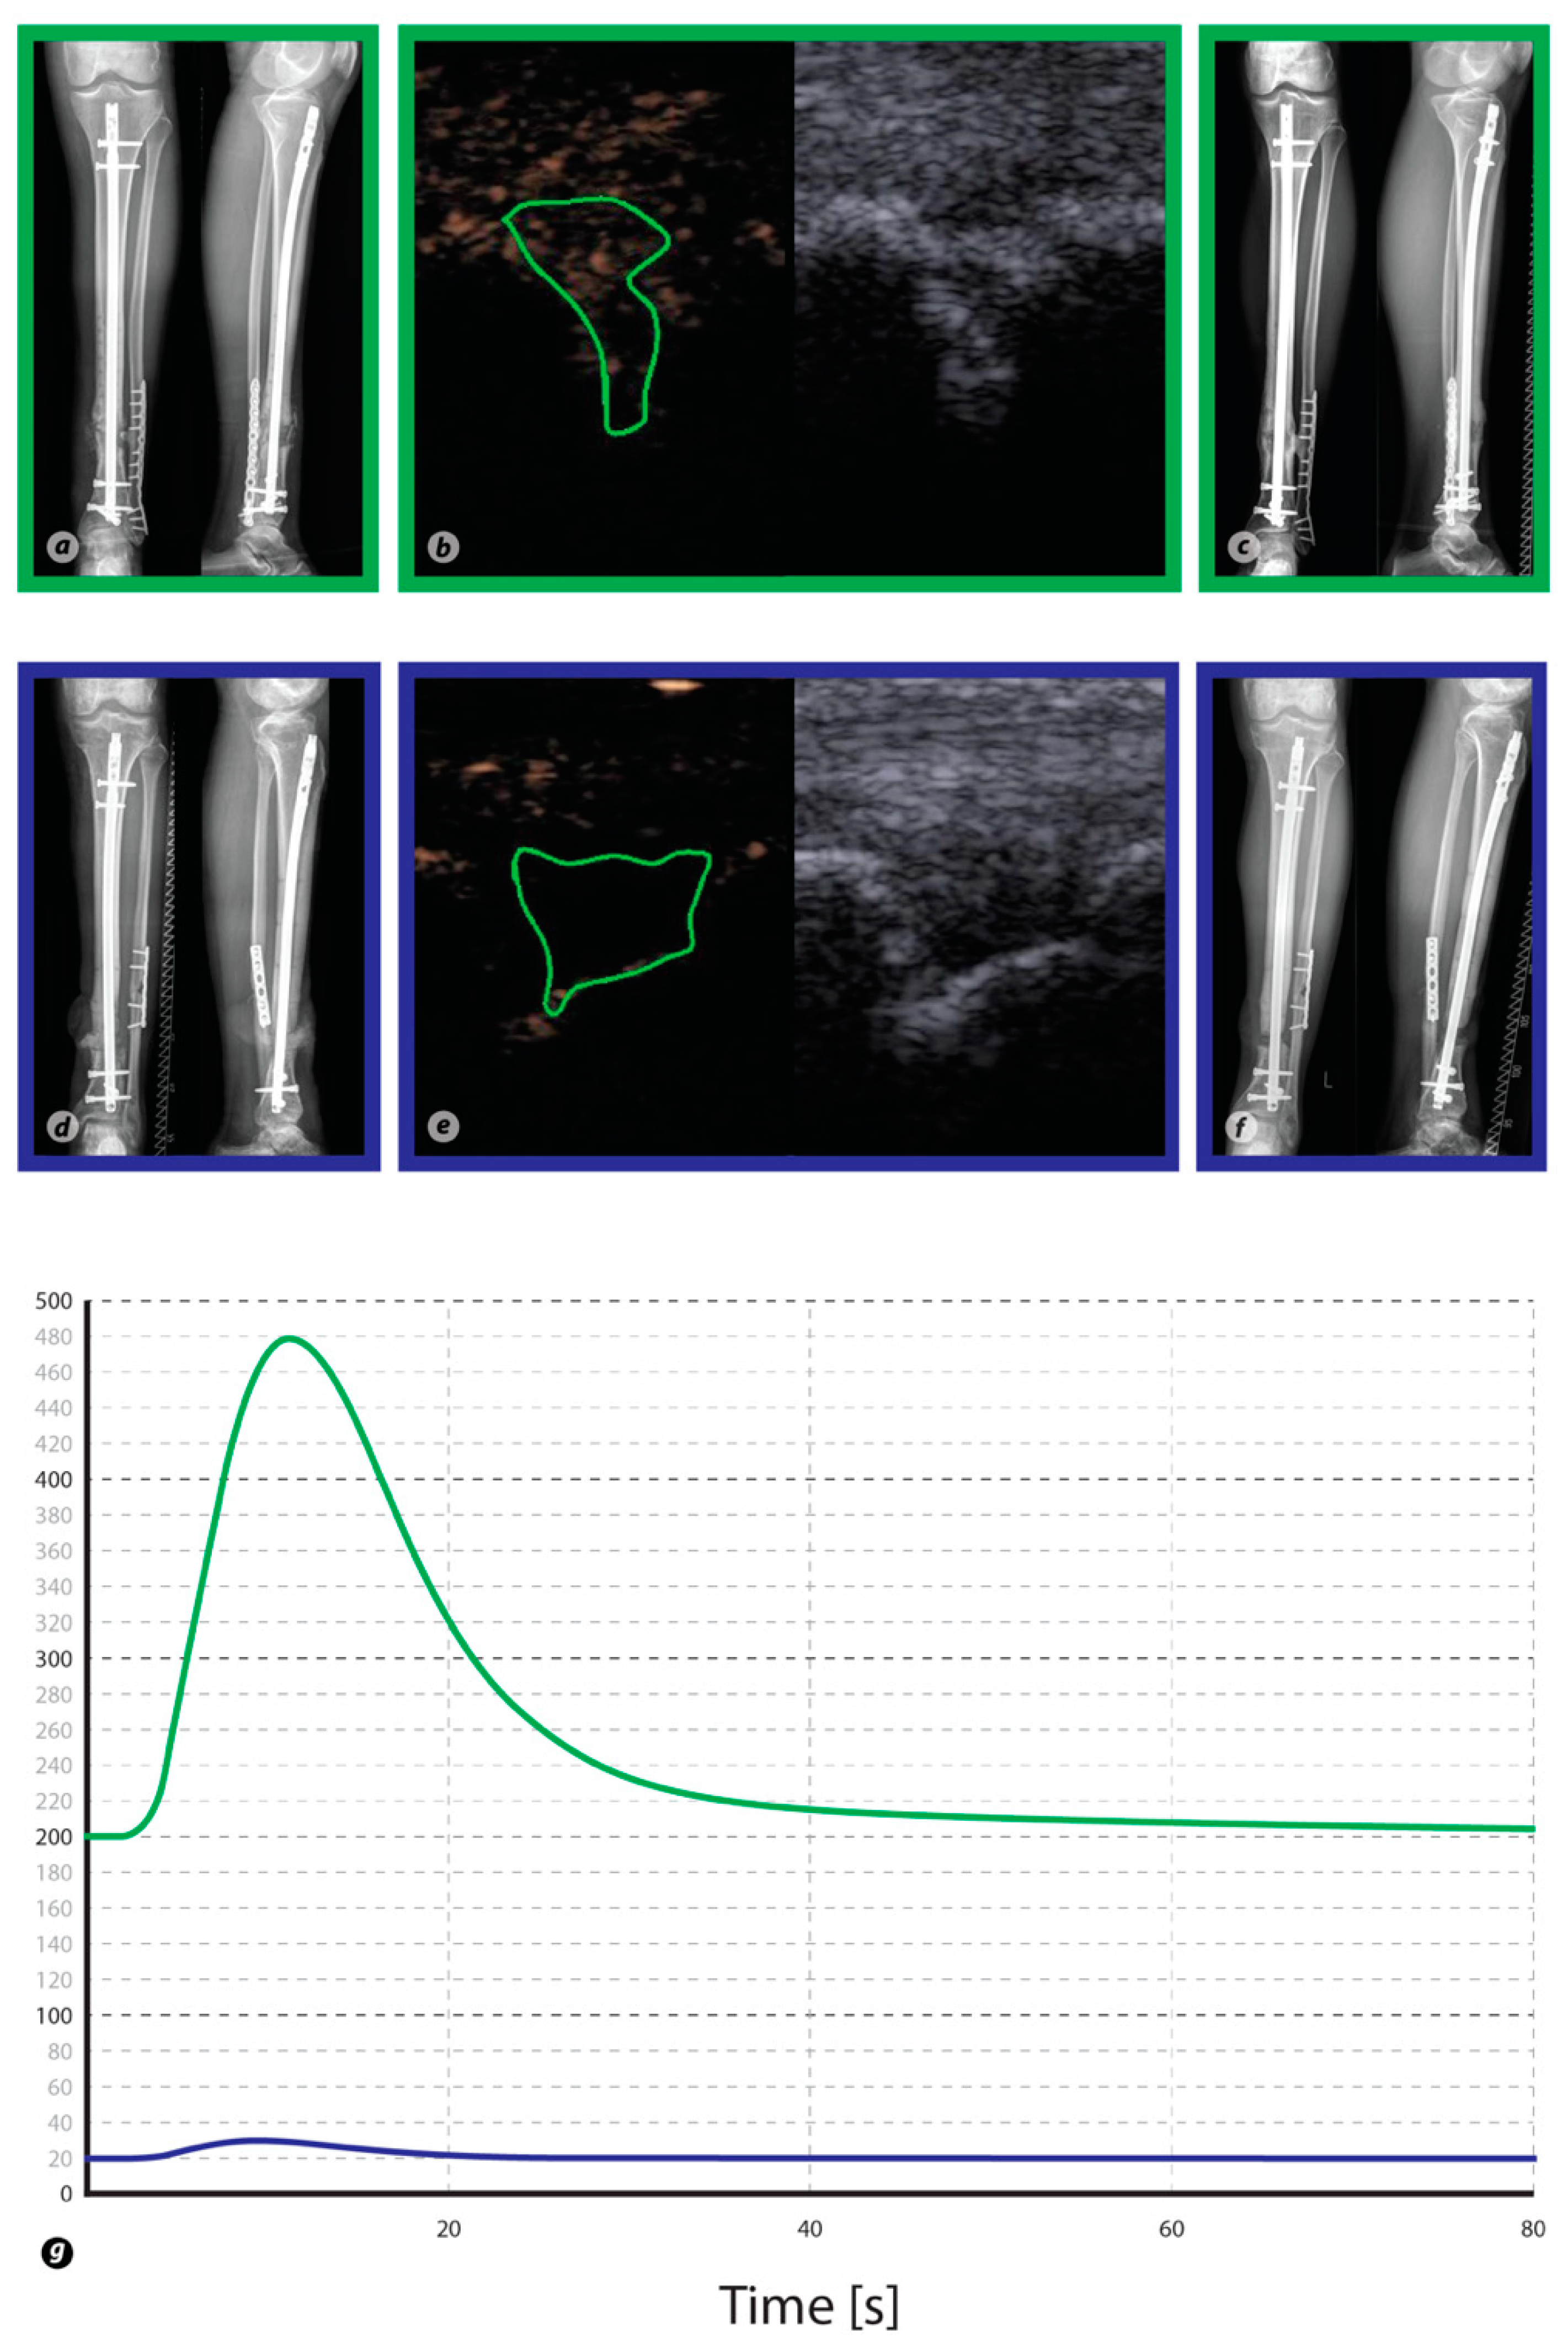

Conventional X-rays of the tibia and fibula as well as ultrasound images are shown for two patients. In particular, images in green rectangles derive from a Responder to the therapy, whereas images in blue rectangles derive from a Non-Responder. Panel (a,d) was taken prior to treatment, whereas (c,f) was taken 6 months after treatment and illustrates the respective outcome of therapy. Contrast-enhanced ultrasound images before (right side) and after contrast enhancement (left side) for each patient (b,e). The region of interest (irregular green shape) is placed into the non-union gap, and a time–intensity curve is generated by the VueBox quantification software (g). The time–intensity curve of the healing non-union exhibits stronger contrast enhancement than in persistent non-union.

Preoperative CEUS quantification of the included tibial non-unions revealed a higher WiR in patients not responding to the non-union treatment compared to patients that showed successful non-union consolidation (WiR: G1: 35.14 ± 11.32 a.u. versus G2: 50.43 ± 23.17 a.u., p > 0.05). In addition, Responders to the therapy had a slower contrast inflow with a mean RT of 16.38 ± 6.93 s versus 8.96 ± 1.69 s in G2 (p > 0.05). It took 26.8 ± 10.2 s on average in G1 for the contrast agent to reach the signal intensity peak (TTP in G2: 10.6 ± 1.7 s, p > 0.05) and the mean PE was lower than in G2 (PE in G1: 189.17 ± 57.16 a.u. versus G2: 218.63 ± 95.65 a.u., p > 0.05). The postoperative WiR was higher in Responders compared to Non-Responders (WiR in G1: 106.59 ± 34.45 a.u. versus G2: 46.91 ± 21.47 a.u., p > 0.05). Furthermore, postoperative contrast inflow was faster in G1 than in G2 (RT in G1: 5.1 ± 1 s versus G2: 15.5 ± 4.2 s, p > 0.05) and the signal intensity peak was higher (PE in G1: 318.82 ± 98.56 a.u. versus G2: 252.39 ± 92.11 a.u., p > 0.05) and reached in a shorter amount of time (TTP in G1: 9.7 ± 1.5 s versus G2: 20.1 ± 4.0 s, p > 0.05) (Figure 3) in Responders to the therapy (Table 2).